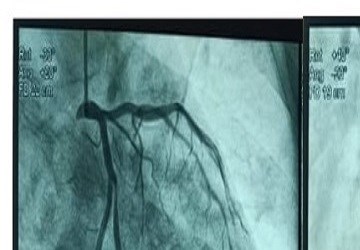

Hành vi bỏ qua bữa ăn sáng và ăn tối muộn có liên quan đến tiên lượng nặng ở bệnh nhân sau nhồi máu cơ tim cấp có ST chênh lên....